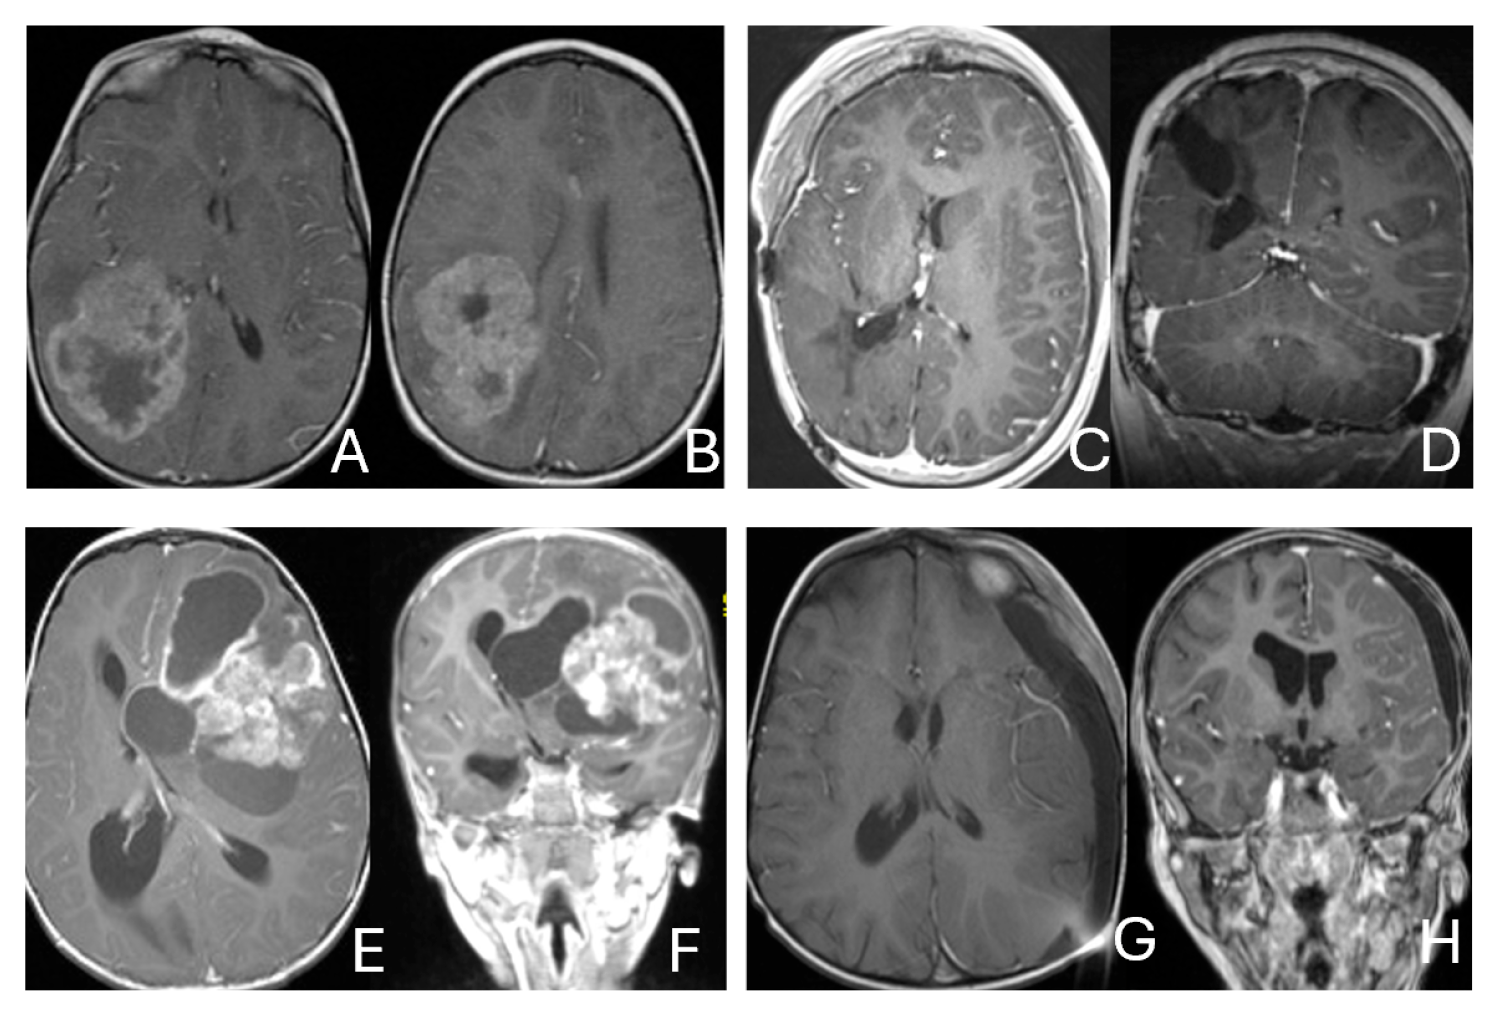

4.13.3. Infratentorial ATRTs:

The cerebellar peduncular, vermis, and CPA/CMF are common site of ATRTs. Most ATRT-TYR tumors arise from the middle cerebellar peduncle and inferior vermis [76] and can extend exophytically into the cerebellopontine angle (CPA) and cerebellomedullary fissure (CMF). ATRT-MYC tumors can originate from cranial nerves in the CPA, producing imaging appearances that overlap with TYR tumors; however, the age distribution differs, with TYR typically affecting much younger children than MYC. Infratentorial ATRTs frequently mimic posterior fossa ependymomas in their location and propensity to extend into the CPA and fourth ventricle, but ATRTs tend to be more infiltrative, whereas ependymomas are usually expansile and less invasive [77]. Consistent with this pattern, the European Rhabdoid Registry reports cranial nerve involvement occurs in approximately 3% of ATRT cases and is most often associated with the MYC subgroup [62]. One female patient with CPA ATRT of CPA, who was notably the oldest in this cohort, had a tumor that likely originated from the vestibular nerve, without involvement of the brainstem or cerebellum. (Figure 12).

Figure 12.

CPA ATRT. (A–D): MR images ((A): axial; (B): coronal) of a 20-year-old girl, the oldest in this cohort, who presented with left-sided hearing loss and partial facial weakness, reveal ATRT that appears to originate from the vestibular nerve. Surgical findings and post-resection MR images ((C): axial; (D): coronal) indicate no tumor invasion into the cerebellum or brainstem, which contrasts with typical presentations of infantile ATRT.